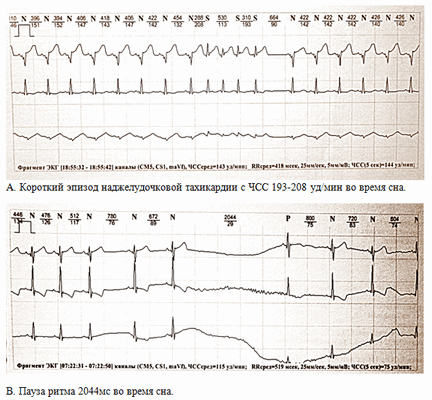

Рисунок 1. Фрагменты суточного мониторирования ребёнка С., 21 сутки.

2. По результатам холтеровского мониторирования у недоношенных новорожденных, особенно рожденных с экстремально низкой массой тела, выявляется более высокий базовый уровень частоты сердечных сокращений и, соответственно, ригидный циркадный профиль, в сочетании с более низкими минимальными значениями и более продолжительными паузами ритма.